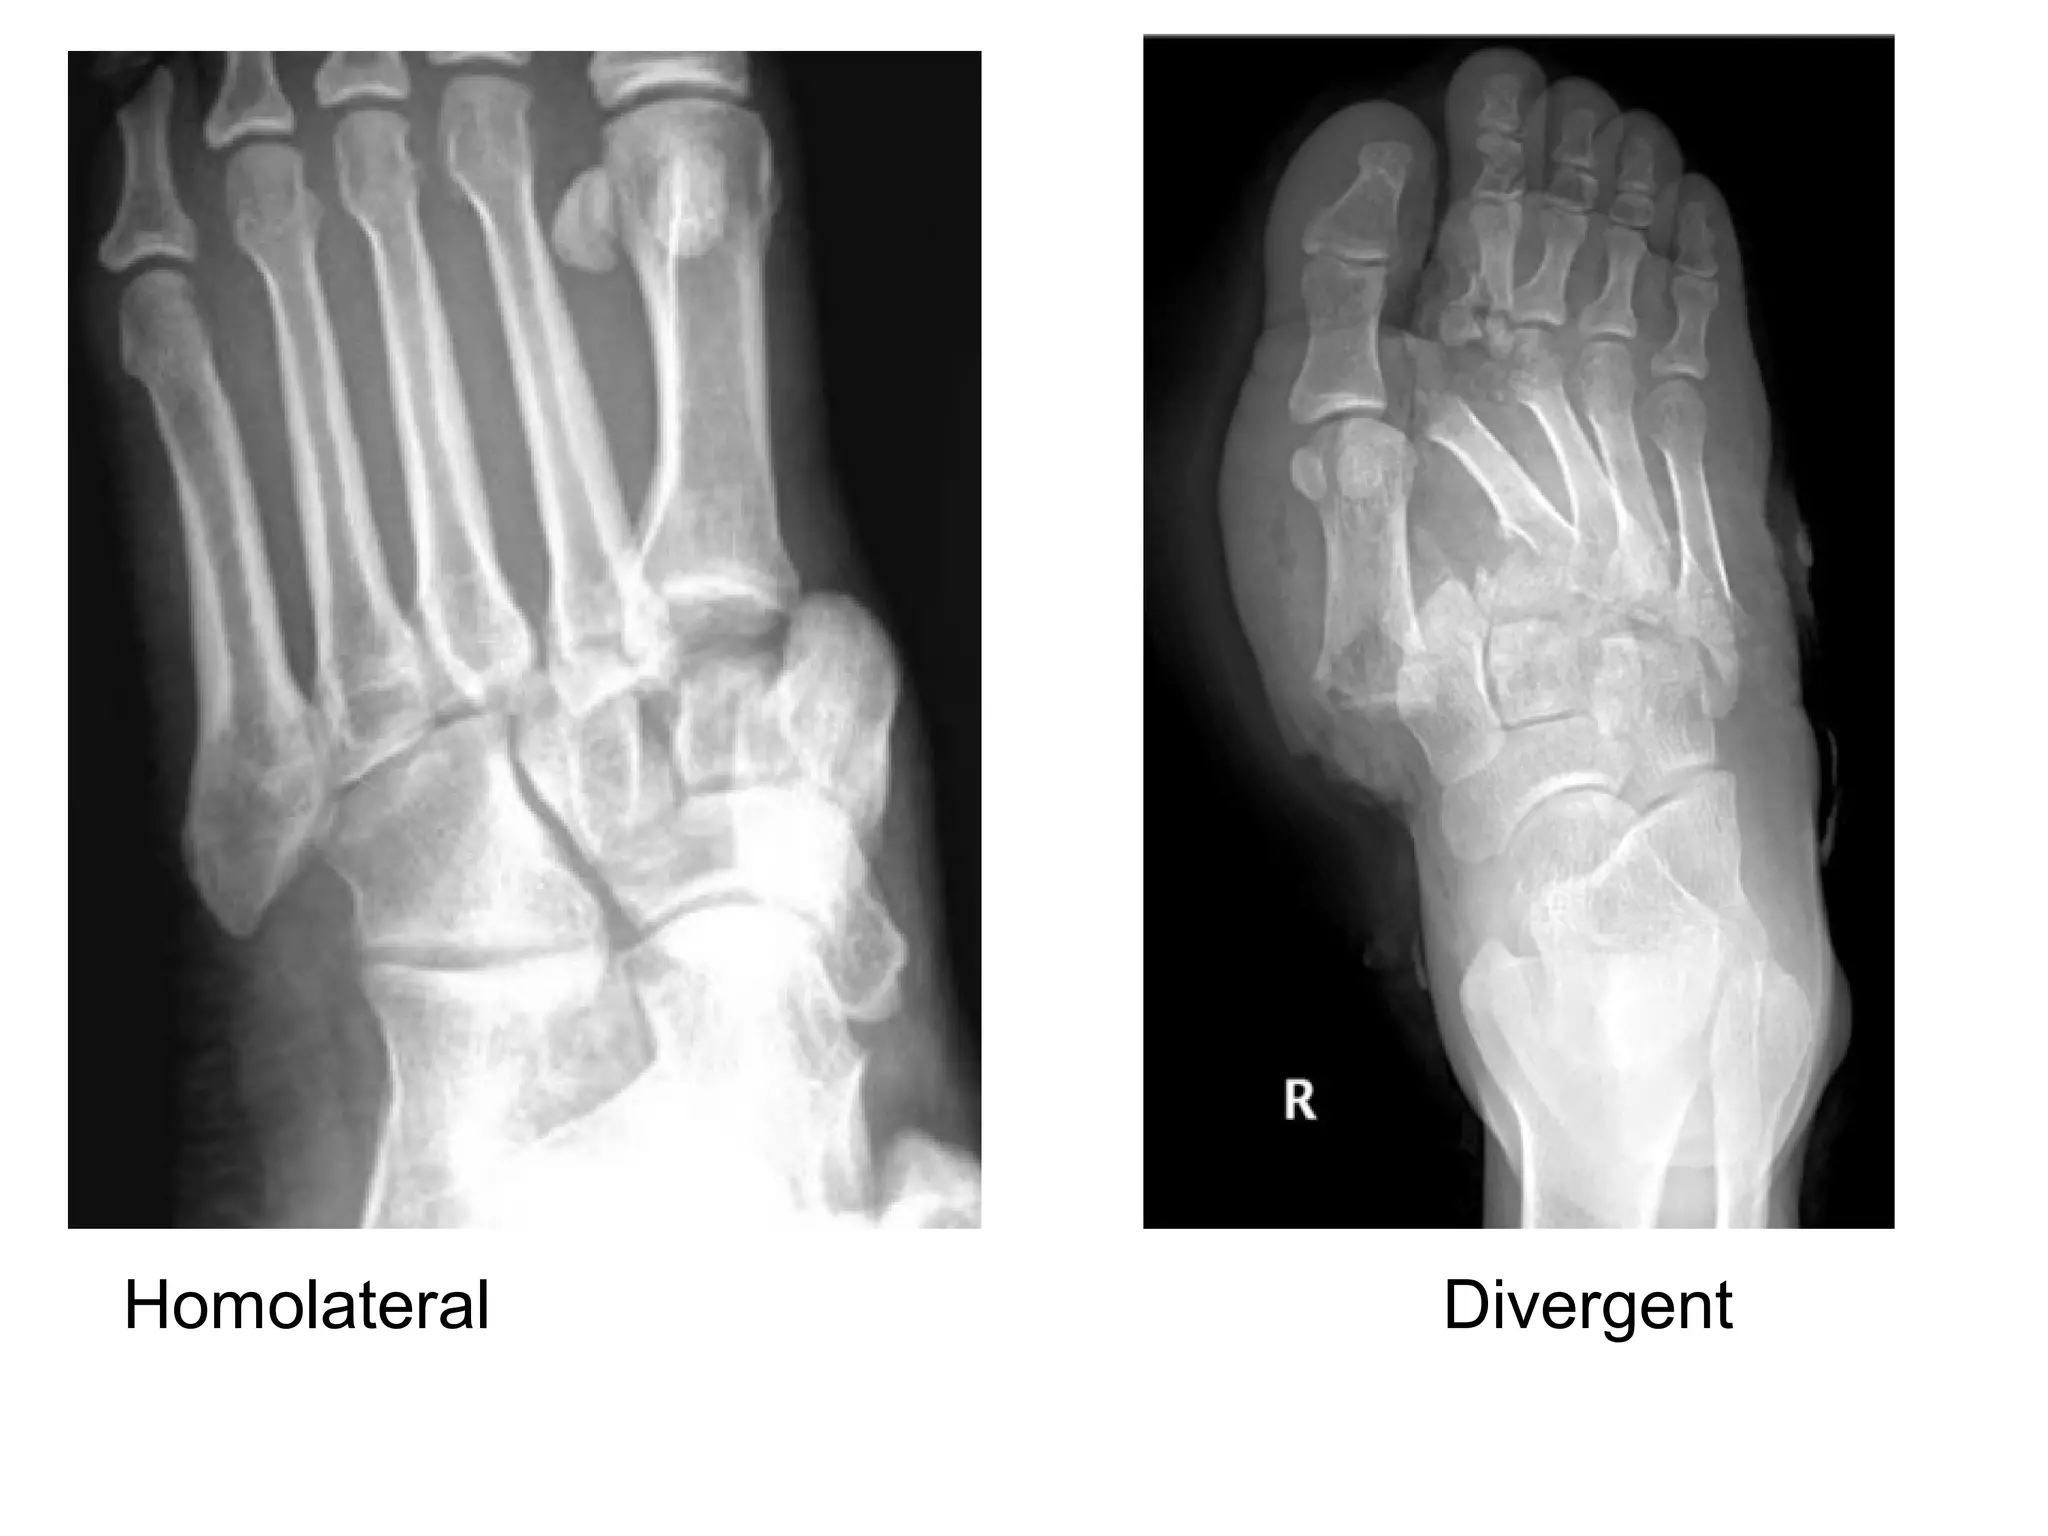

**N.B. : Lisfranc dislocation

-Two types :

1-Homolateral :

-A homolateral injury is the lateral displacement of the

1st to 5th metatarsals , or of 2nd

to 5th metatarsals where

the 1st MTP joint remains congruent

2-Divergent :

-A divergent injury is the lateral dislocation of the 2nd to

5th metatarsals with medial dislocation of the

1st metatarsal

Homolateral Divergent